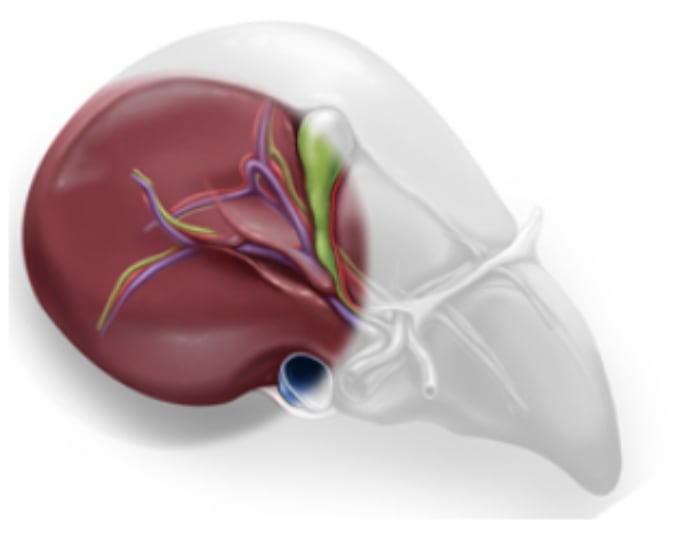

6. Semiposition offers better exposure of the right posterior segments and lifts the right hepatic vein higher than the vena cava to reduce hepatic venous bleeding (4)

The right hepatic vein is higher than the vena cava: P (right hepatic vein) < P(vena cava)